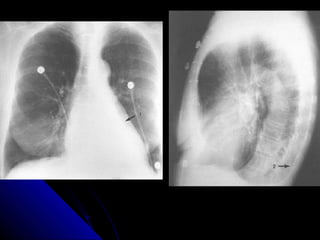

NNoodduullee//mmaassss

NNoodduulleess aanndd mmaasssseess iinn tthhee lluunngg aappppeeaarr aass

rroouunndd wwhhiittee lleessiioonnss.. IIff tthhee lleessiioonn mmeeaassuurreess lleessss

tthhaann 33 ccmm,, iitt iiss ccaalllleedd aa nnoodduullee.. IIff iitt iiss llaarrggeerr tthhaann

33 ccmm,, iitt iiss ccaalllleedd aa mmaassss..

AA nnoodduullee//mmaassss iiss ccaauusseedd bbyy eeiitthheerr aa mmaalliiggnnaanntt

((ee..gg.. lluunngg ccaanncceerr,, mmeettaassttaassiiss)) oorr bbeenniiggnn pprroocceessss

((ee..gg.. hhaammaarrttoommaa,, ggrraannuulloommaa))..

PPrriimmaarryy lluunngg ccaanncceerrss tteenndd ttoo hhaavvee iillll--ddeeffiinneedd,,

ssppiiccuullaatteedd bboorrddeerrss.. MMeettaassttaasseess tteenndd ttoo pprroodduuccee

mmuullttiippllee ssmmooootthh rroouunndd lluunngg nnoodduulleess,, oofftteenn ooff

vvaarriiaabbllee ssiizzee.. BBeenniiggnn lleessiioonnss tteenndd ttoo bbee ssmmaallll,,

wweellll ddeeffiinneedd,, ssmmooootthh,, rroouunndd aanndd mmaayybbee ccaallcciiffiieedd..